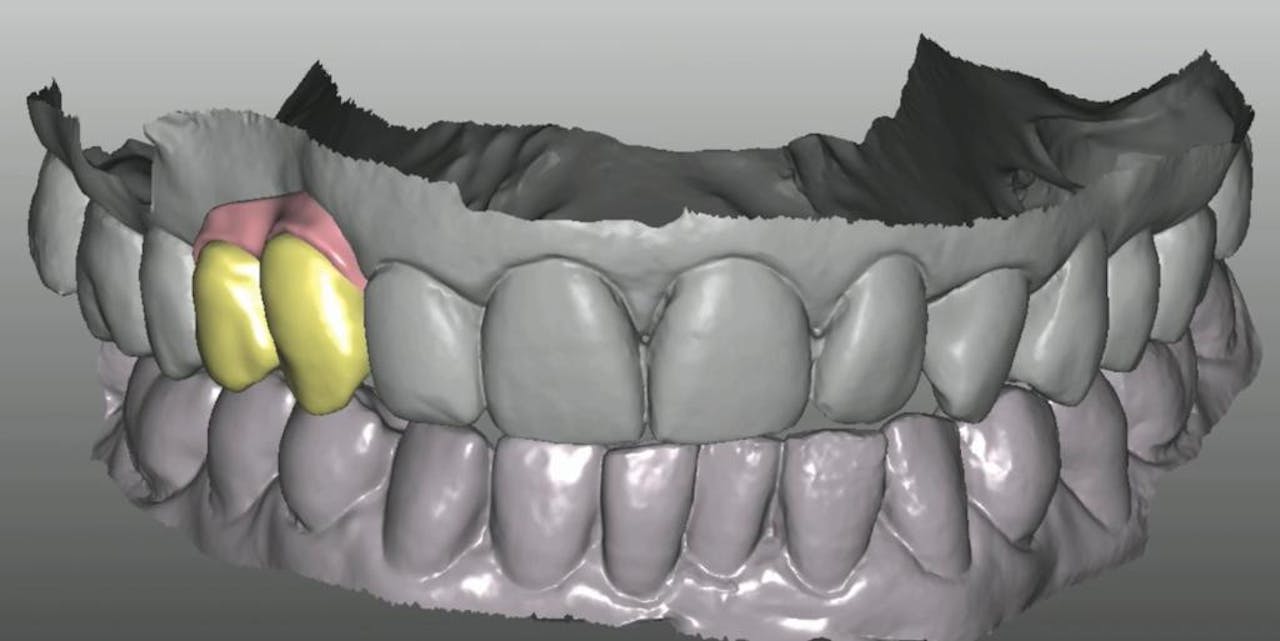

CLINICAL VIDEO Single Implant Placement for Missing Upper Premolar